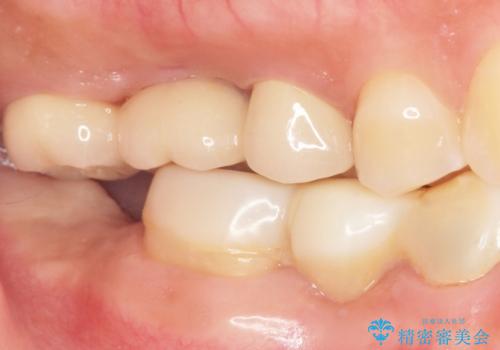

インプラントや入れ歯を使わずに奥歯でしっかり咬むことができるようになり、また見た目も自然だと大変喜んで頂けました。

クラウンの種類:メタルボンドクラウン エコノミー フルベイク